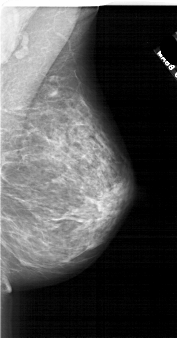

A_1744_1.RIGHT_MLO

RIGHT_MLO LINES 6406 PIXELS_PER_LINE 3361 BITS_PER_PIXEL 12 RESOLUTION 43.5 NON_OVERLAY